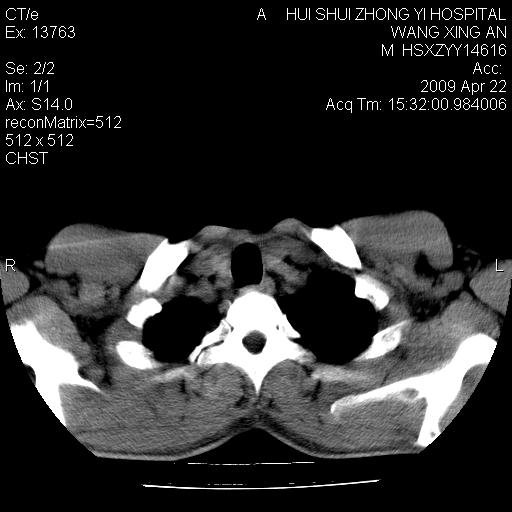

标题: CT19534:患者男、46岁咳嗽、胸痛半月。 [打印本页]

标题: CT19534:患者男、46岁咳嗽、胸痛半月。